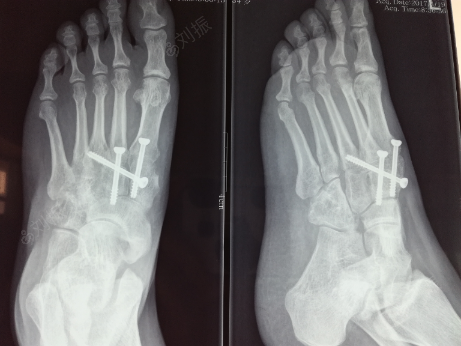

右足第二跖骨基底楔骨骨折并lisfranc损伤的治疗过程

低能量lisfranc损伤的微创治疗.诊断:低能量lisfr - 抖音